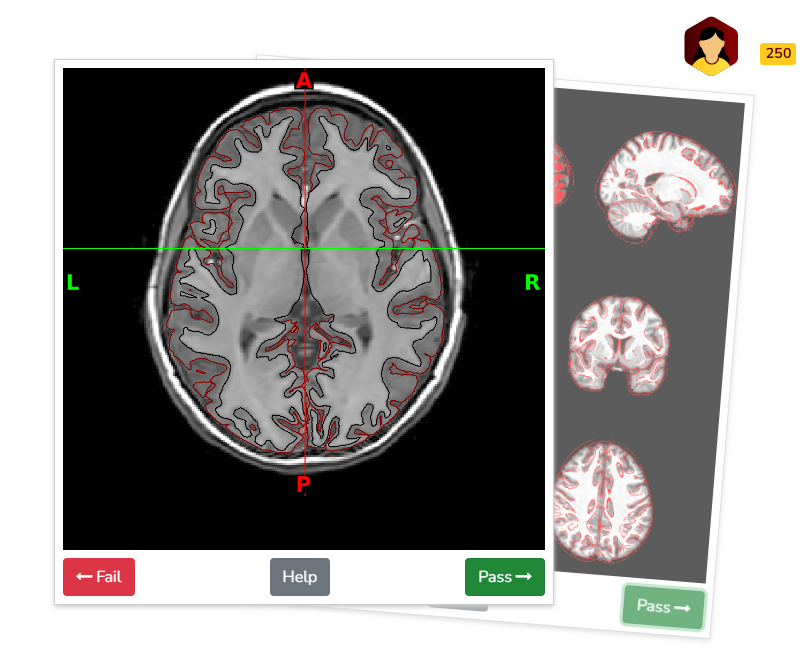

Manual visual inspection remains the gold standard for identifying artifacts in structural and functional derivatives (e.g., from the abcd-hcp-bids pipeline) and diffusion derivatives (e.g., from QSIPrep). To streamline this process, derivative visual reports are integrated into BrainSwipes, a gamified, crowdsourced QC platform built on the open-source Swipes For Science framework. BrainSwipes engages users in evaluating brain image quality through an intuitive interface designed for large-scale studies. After creating an account, users are guided through a brief tutorial that teaches them how to assess derivative images and classify them as pass or fail.

For structural QA, swipers are presented with image slices in coronal, axial, and sagittal planes to assess the accuracy of T1w and T2w surface delineations in differentiating gray and white matter. Images are derived from XCP-D visual reports.

In addition to surface delineation, structural QA also includes atlas registration quality, evaluated by overlaying delineations of the subject’s image onto the atlas, and vice versa. Swipes display nine T1w slices for visual inspection, with three slices per anatomical plane. Quality is assessed based on the alignment of the outer boundaries of the overlaid contours with those of the underlying image, ensuring minimal gaps or misalignments. Images are derived from XCP-D visual reports.

Example quality assessment of surface delineation on BrainSwipes platform (displaying brain in axial plane at level of basal ganglia/putamen):